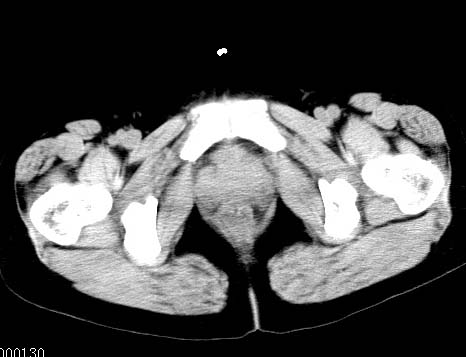

女性 病人 44岁 盆腔 下腹部痛1天!

盆腔内低密度为主混杂等密度及少许囊样与班状钙化影,如果做了肠道准备就好了。支持畸胎瘤。当然做mri会更好

典型的双侧附件畸胎瘤.

盆腔多发畸胎瘤,较为典型。